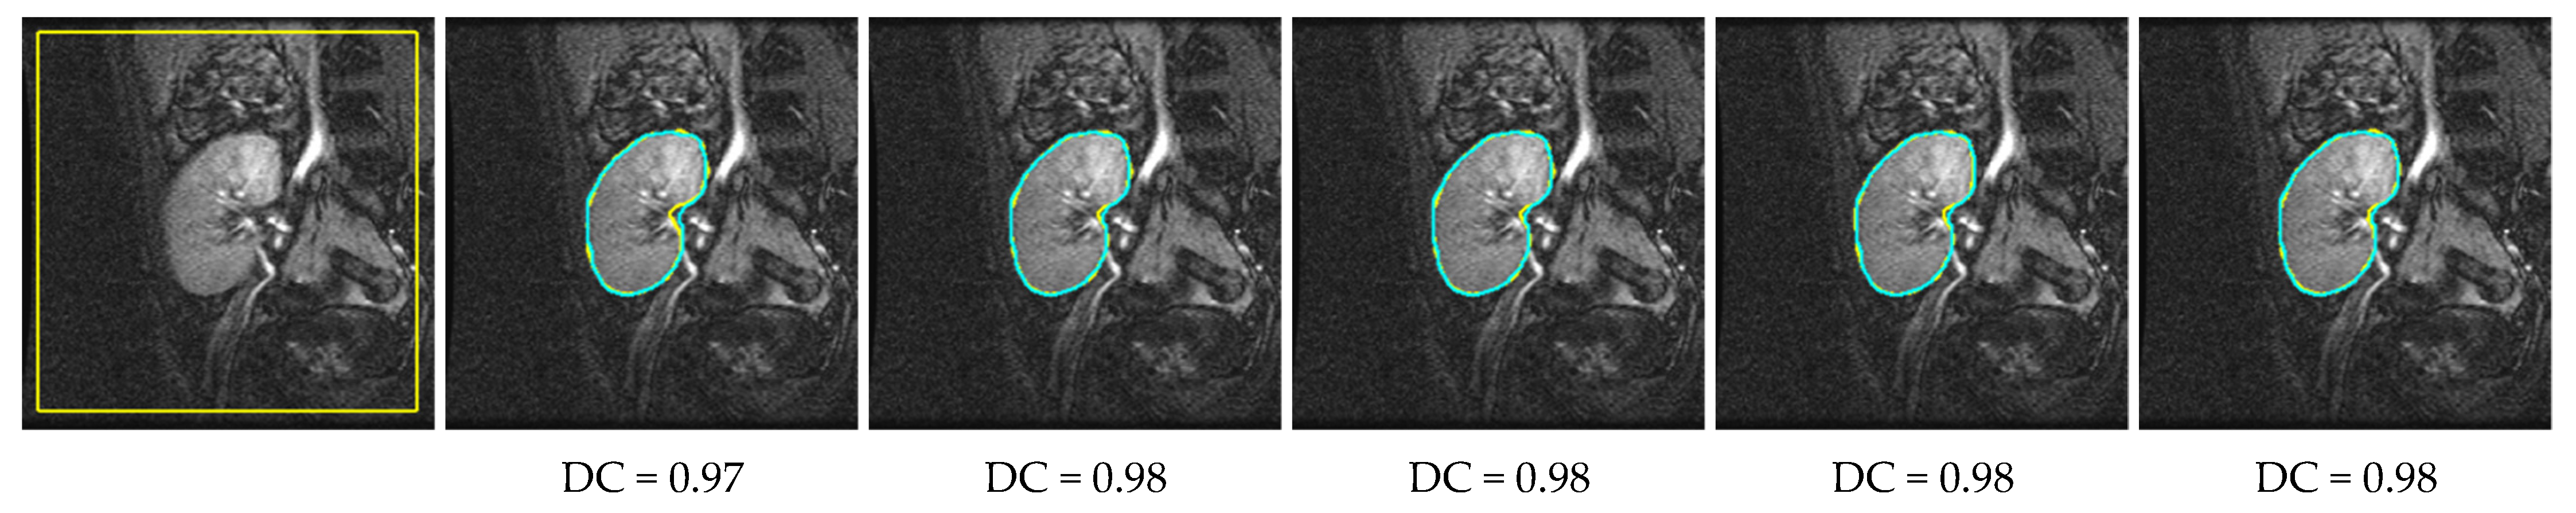

| Method | All DCE-MRIs | Affine-Transformed DCE-MRIs | ||||

|---|---|---|---|---|---|---|

| DC | IoU | 95HD | DC | IoU | 95HD | |

| FCMLS [11] | 0.88 ± 0.10 | 0.79 ± 0.17 | 5.07 ± 7.65 | 0.83 ± 0.10 | 0.72 ± 0.14 | 8.35 ± 7.55 |

| PBPSFL [12] | 0.92 ± 0.06 | 0.87 ± 0.08 | 3.29 ± 5.65 | 0.90 ± 0.07 | 0.83 ± 0.09 | 5.4 ± 7.18 |

| PSFL [13] | 0.91 ± 0.06 | 0.84 ± 0.10 | 3.84 ± 4.56 | 0.87 ± 0.07 | 0.77 ± 0.11 | 6.57 ± 5.03 |

| FML [17] | 0.90 ± 0.08 | 0.83 ± 0.16 | 4.41 ± 6.4 | 0.87 ± 0.08 | 0.76 ± 0.12 | 7.3 ± 5.45 |

| Proposed | 0.94 ± 0.03 | 0.89 ± 0.05 | 2.2 ± 2.32 | 0.93 ± 0.05 | 0.88 ± 0.06 | 2.5 ± 2.7 |